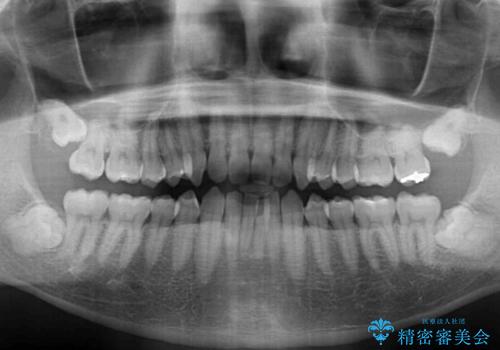

- 上下前歯のデコボコと深い咬み合わせを気にして来院された患者様です。

インビザラインによる上下歯列の拡大と、IPR(歯と歯の間を削る)にるスペースの獲得により、前歯のデコボコとディープバイトを改善することとしました。